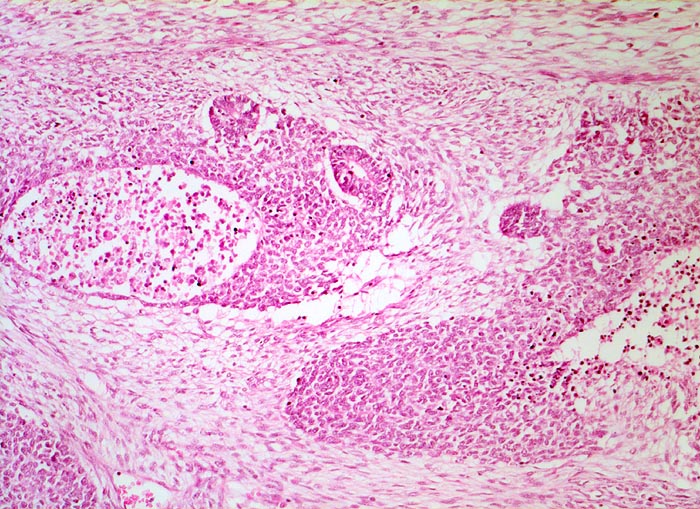

Wilms-Tumor

maligner Tumor

Niere

Alle drei Komponenten des Wilms Tumors sind auf diesem Bild sichtbar. Das lockere spindelzellige Stroma, die zelldichte Blastemkomponente mit Nekrosen und Einschluss epithelialer Elemente in Form von Tubuli.

Graubrauner scharf begrenzter weicher Tumor mit fokalen Nekrosen und Einblutungen.

Palpabler Tumor im linken Hemiabdomen. Makrohämaturieepisode.

Histologie

50